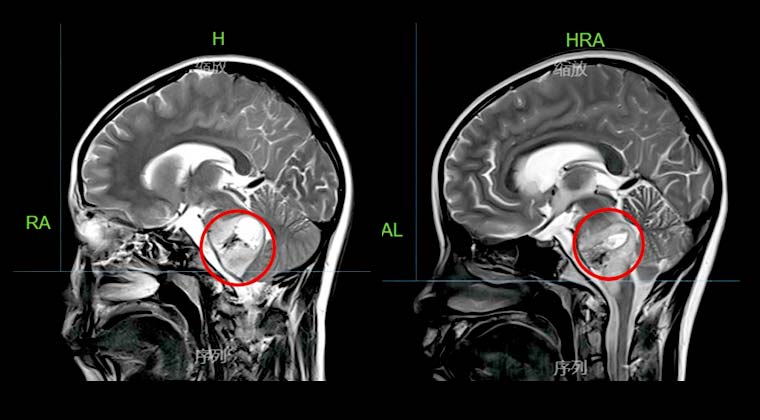

① Случай 1:

Пациентка: девочка, 10 лет

Диагноз: Злокачественная опухоль головного мозга (глиома)

Симптомы: Слабость в ногах и руках, нечёткая речь

Лечение с помощью Киберножа начато 102020, доза облучения — PTV 25 Гр / 5 Гр / 5 сеансов

Через 2 месяца после лечения контрольная визуализация показала небольшое уменьшение очага опухоли ствола мозга. Сознание восстановлено, речь значительно улучшилась, движения конечностей постепенно нормализовались.

До лечения: После лечения: